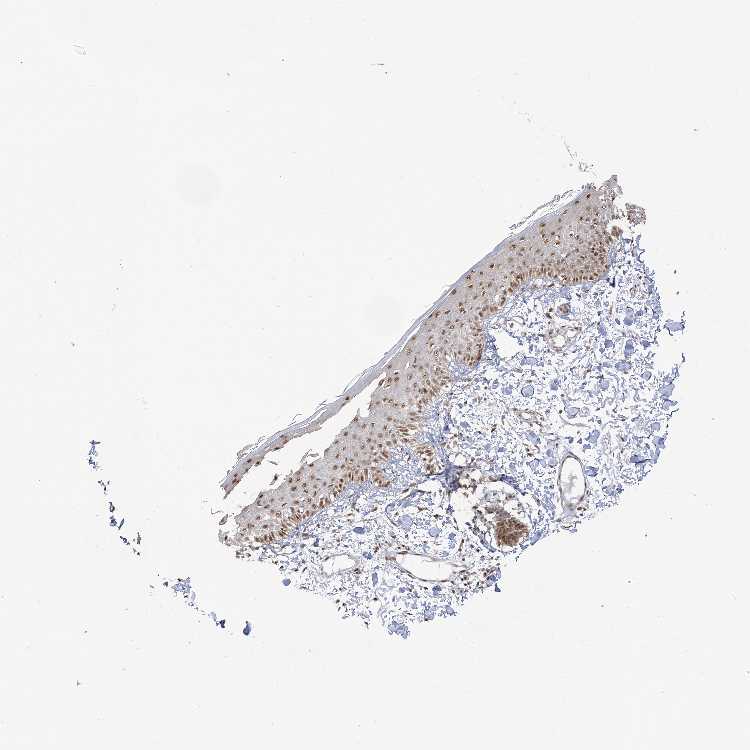

SKIN 1 - Antibody stainingi

Antibody staining in the annotated cell types in the current human tissue is reported as not detected, low, medium, or high, based on conventional immunohistochemistry profiling in selected tissues. This score is based on the combination of the staining intensity and fraction of stained cells.

Each image is clickable and will lead to virtual microscopy that enables deeper exploration of all samples and also displays staining intensity scores, fraction scores and subcellular localization as well as patient and tissue information for each sample.

Antibody HPA034962

Cells in basal layer Medium

Cells in corneal layer Not detected

Cells in granular layer Medium

Cells in spinous layer Medium

Endothelial cells Medium

Extracellular matrix Not detected

Fibrohistiocytic cells Medium

Langerhans cells Medium

Lymphocytes Medium

Melanocytes Medium

Vascular mural cells Medium